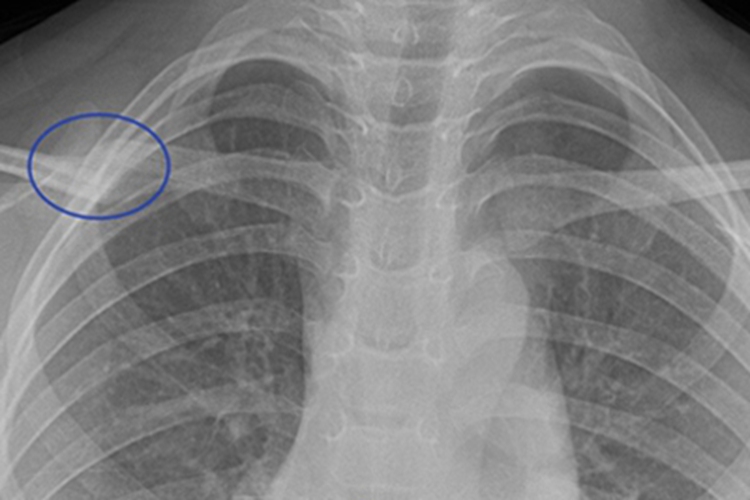

锁骨畸形愈合表现为X片上可见骨痂或骨刺出现,还会出现肌腱短缩、成角畸形等症状。

锁骨骨折畸形愈合可在X线片上看到骨痂或骨刺的出现,同时还会出现肌腱缩短、成角畸形及骨短缩、伪翼状肩胛骨等症状。肌腱短缩会影响患者的上肢力量,患者常感到上肢无力、易疲劳和疼痛。骨畸形侵蚀到胸廓出口往往会导致患者麻木和感觉异常。轻度的畸形愈合一般不出现疼痛或其他症状。